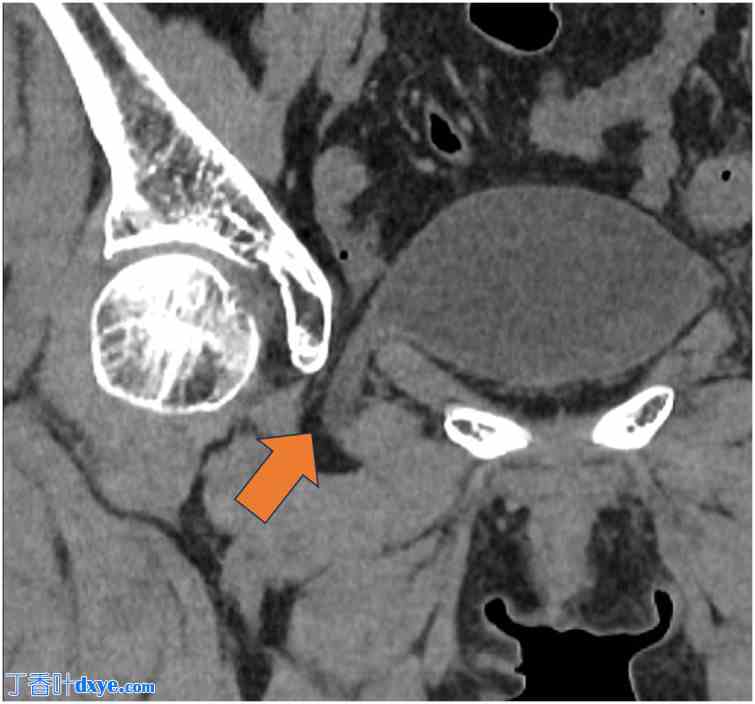

一名74岁女性被诊断为闭孔膀胱疝,并转诊至我科行手术治疗。该患者最初因便血入院,被诊断为缺血性结肠炎。诊断时进行的CT检查意外发现小肠闭孔疝(图1)。次日复查CT显示膀胱经闭孔疝出(图2)。因此,她随后被转诊至院进行进一步评估和治疗。她的缺血性结肠炎经保守治疗后痊愈。患者身高151.7 cm,体重45.3 kg,BMI为19.7。她没有与闭孔膀胱疝相关的症状。既往病史包括子宫肌瘤和阑尾炎,分别接受了腹腔镜下子宫肌瘤切除术和阑尾切除术。她不吸烟,偶尔饮酒。院CT检查证实膀胱经闭孔疝出,确诊为闭孔膀胱疝(图3)。在详细解释病情及相关风险后,患者同意接受手术治疗。

图2. 次日转诊医院的CT扫描。箭头:膀胱经闭孔疝出。

2.jpg